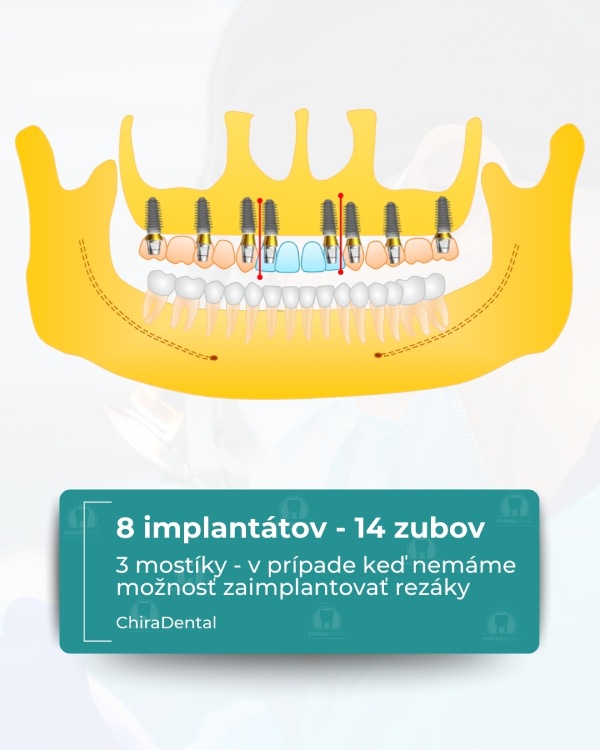

Moderné technológie umožňujú rýchlo, spoľahlivo a esteticky obnoviť celú čeľusť, a to aj v zložitých prípadoch. Ponúkame niekoľko kompletných rehabilitačných systémov založených na počte implantátov a úrovni fixácie budúcej štruktúry. Možnosť 1 - All-on-4 (Základné riešenie) Táto metóda je vhodná pre pacientov so zníženým objemom kosti alebo pre tých, ktorí chcú nové zuby čo najrýchlejšie. Čo robíme: Inštalujeme 4 implantáty do hornej alebo dolnej čeľuste; V prípade potreby vykonáme augmentáciu kosti a plastiku ďasien počas tej istej návštevy; Nasledujúci deň odoberieme odtlačky pre dočasnú štruktúru; Po 3-5 pracovných dňoch pacient dostane dočasné kovovo-akrylátové zuby na dlhodobé nosenie. Výsledok: približne 10 nových zubov, ktoré umožňujú pohodlné žuvanie a úsmev. Po 3-6 mesiacoch vykonávame trvalé rekonštrukcie s použitím kovovo-keramiky alebo zirkónu. ⭐ Možnosť 2 — All-on-6 (štandardné riešenie) Optimálna možnosť pre pacientov, ktorí vyžadujú väčšiu stabilitu a väčšiu žuvaciu záťaž. Čo robíme: Inštalácia 6 implantátov so súčasnou augmentáciou kosti a ďasien; Odtlačky sa robia nasledujúci deň;Dočasné kovovo-akrylátové korunky sa inštalujú po 3-5 dňoch.

Výsledok: kompletný oblúk 14 zubov. Definitívna rekonštrukcia (kovovo-keramika alebo zirkón) sa vykonáva po 3-6 mesiacoch.